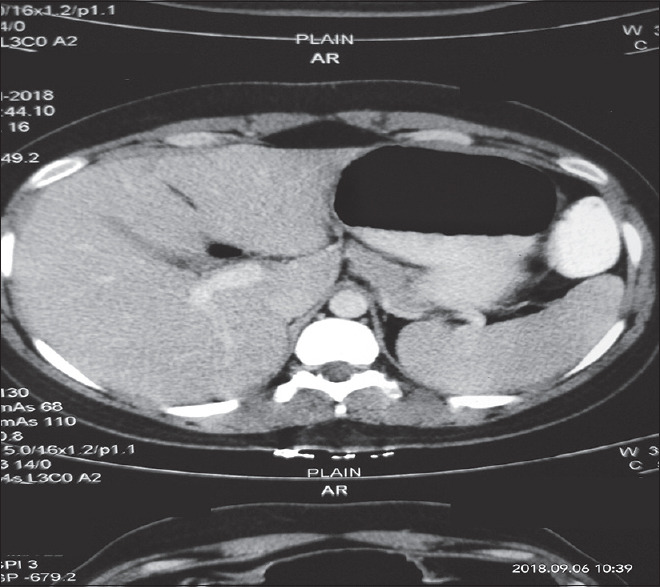

本病例报告描述了一种罕见的胃血管球瘤,它是一种间质起源的肿瘤。它们通常是良性的,占所有胃肠道软组织肿瘤的近1%。由于缺乏特异性特征,术前几乎无法诊断,常被误认为胃肠道间质瘤(gist)。在我们的医院设置,24岁的女性,表现为右腰腹痛,经过彻底的检查导致术前诊断为GIST,并进行远端胃切除术并Roux-en-y吻合。然而,术后病理和免疫组化检查结果与胃球囊瘤的诊断一致。在GIST-1 (DOG-1)上发现的无反应性可用于诊断肾小球瘤,有助于排除DOG-1阳性的GIST的诊断。因此,我们认为,基于免疫组织化学结果的鉴别诊断可以导致准确的术前诊断和进一步有针对性的手术干预。

This case report describes glomus tumor of the stomach, a rare entity, which is a mesenchymal origin tumor. They are generally benign and account for nearly 1% of all gastrointestinal (GI) soft-tissue tumors. They are almost impossible to diagnose preoperatively because of the lack of specific characteristics and are often mistaken for GI stromal tumors (GISTs). In our hospital setup, a female aged 24 years, presented with right lumbar abdominal pain which after a thorough workup leads to the preoperative diagnosis of GIST, and distal gastrectomy with Roux-en-y anastomosis was done. However, pathological and immunohistochemical findings done after the surgery were found consistent with the diagnosis of gastric glomus tumor. Discovered on GIST-1 (DOG-1) nonreactivity is considered for the diagnosis of glomus tumor which helps in excluding the diagnosis of GIST, which is positive for DOG-1. Hence, it was concluded that differential diagnosis on the basis of immunohistochemical findings can lead to an accurate preoperative diagnosis and further targeted surgical intervention.